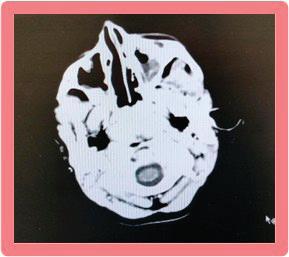

кортикалните и менингеални кръвоносни съдове и води до мозъчно възпаление и инфаркт. Развива се характерен базален менингит, засягат се предимно III, VI и VII ЧМН и се развива обструктивна хидроцефалия→адхезия + облитериращ васкулит + енцефалит или миелит.

Етиологичната диагноза на туберкулозния менингоенцефалит по обективни причини е възможна в 6-10% от заболелите деца. Поради това диагнозата е комплексно обусловена. Епидемиологичната анамнеза, симптоматиката на базален менингит и характеристиката на ликворния синдром са патогномонични и поставят диагнозата. Абсолютно необходимо е диагностичния процес да продължи с туберкулинов тест на Манту, микробиологично изследване на ликвор (директна микроскопия, посявка на MGIT, PCR real time, BACTEK); SPOT TB; QFT in tube; Рентгеново изследване на белите дробове; КАТ, ЯМР на мозъка.

Беше осъществено Рьо на бели дробове: липсват рентгенови данни за патологични засенчвания в белодробния паренхим двустранно. К.д. синуси – свободни. Сърце и медиастинум – б.о. Контролна КАТ на главен мозък: екстремно разширени вентрикулни отдели на ликворната система. Намален

цистерни. Заключение: КТ данни за тежка вътрешна хидроцефалия